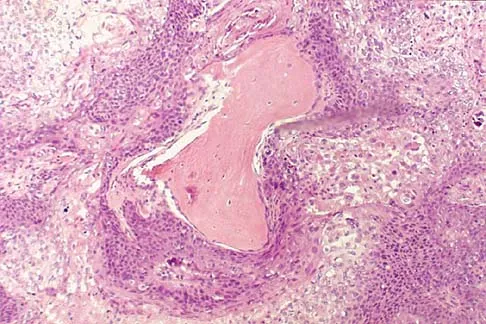

A 69-year-old man has a painful slow-growing lesion of the distal phalanx of his thumb. History reveals that he has had chronic osteomyelitis of the thumb for the past 12 years. The radiograph and biopsy specimens are seen in Figures 9a through 9c. Treatment should consist of

Explanation

The diagnosis is squamous cell carcinoma. The radiograph shows a destructive lesion, and the histologic slides demonstrate squamous cells invading bone. The preferred treatment for squamous cell carcinoma is wide resection; however, in this location a wide margin can be achieved only with amputation. Overall survival in patients with squamous cell carcinoma secondary to chronic osteomyelitis is not significantly worse than that expected for age-matched controls. Dell PC: Hand, in Simon MA, Springfield D (eds): Surgery for Bone and Soft Tissue Tumors. Philadelphia, PA, Lippincott-Raven, 1998, pp 405-420.